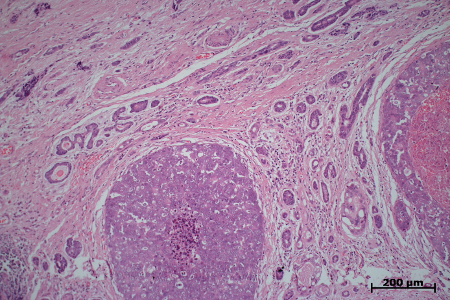

4. Zu den schon länger bekannten brustdrüsenanalogen Karzinomen gehört schließlich das Speichelgangkarzinom. Den Klinikern ist diese Tumorgruppe als die mit dem höchsten Progressionsrisiko unter den malignen Speicheldrüsentumorerkrankungen bekannt. Weniger bekannt ist, dass unter diesen Neoplasien (ähnlich wie bei Mammakarzinomen) Steroidrezeptor-Expressionen (speziell Androgenrezeptorexpressionen) und Her2-Amplifikationen vorkommen. Erstere treten in bis zu 80% dieser Tumorgruppe, letzere in bis zu 20% auf. Damit eignen sich Patienten mit Speichelgangkarzinomen auch besonders für zielgerichtete („maßgeschneiderte“), dabei nebenwirkungsarme systemische Behandlungsmodalitäten. Ein erstes Signal für ein solches multimodales Therapiekonzept geht von der 2014 aufgelegten EORTC-Studie 1206 aus.

Speichelgangkarzinom